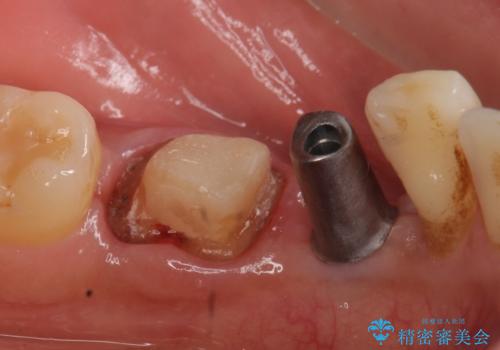

歯列矯正は御希望されなかったため左下4、5番目の歯を抜歯し、インプラントによる欠損補綴を行いました。

左下6も再根管治療後、オールセラミッククラウンによる補綴を行いました。

カスタムアバットメントについて

カスタムアバットメントは患者様それぞれの歯茎に合わせて製作されたオーダーメイドのアバットメントです。

既製のアバットメントに比べ適合がよく、高い清掃性を誇ります。

今回用いたオールセラミッククラウンはジルコニアフレームという白い素材の上にセラミックを盛っているため、審美性が非常に高いのが特徴です。

また、ジルコニアは人工ダイヤモンドの材料にも使われているほど高い強度を持っており、そのためオールセラミッククラウンは審美性だけでなく、奥歯やブリッジの補綴も可能とするクラウンです。